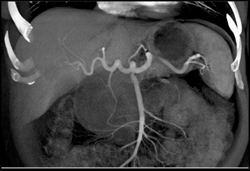

Hemangioma